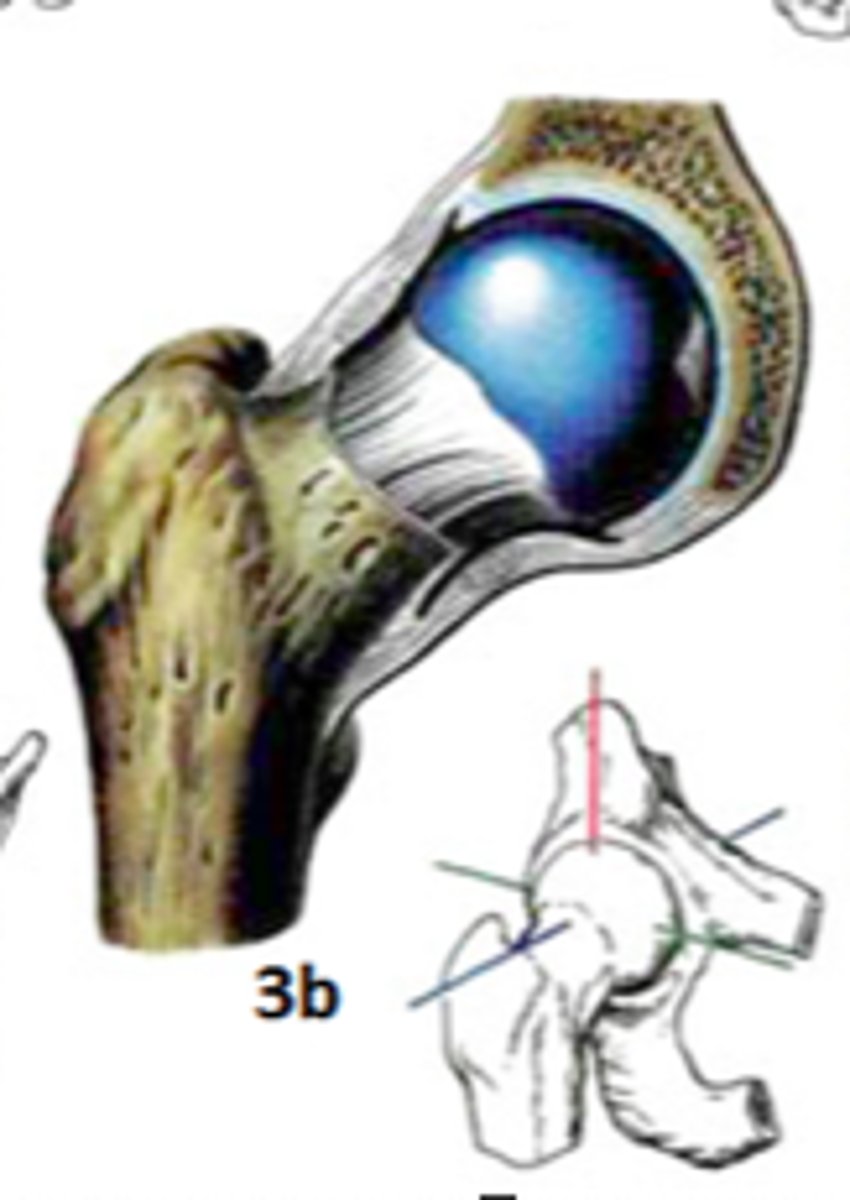

Art. Spheroidea

Art. humeri

Art. humeroradialis

Art. talocalcaneonavicularis